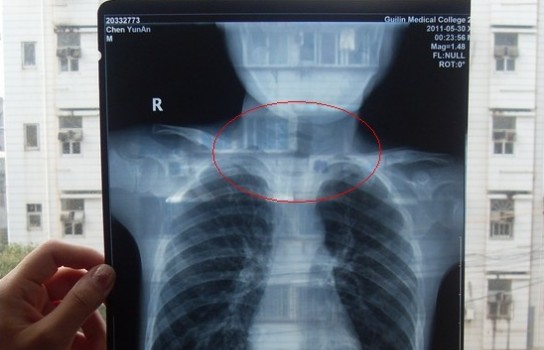

胸部正位X光片圖

2011年5月29日下午,陳先生的兒子安安出現嘔吐、肚子疼痛等癥狀。陳先生立即將兒子送往醫學院附院,根據醫生開出的會診單,分別對安安做了腹部立臥位2次和胸部正位1次共3次X光片檢查、診斷。醫生看X光片后排除了腸梗阻病因,判斷是闌尾炎。經過治療,不久安安身體痊愈。

可是,陳先生的一次偶然發現,讓他們一家過上了提心吊膽的日子。因為,在安安出院一個月后,陳先生偶然翻出孩子治療期間的X光片。發現在X光片中,孩子的生殖器官以及甲狀腺等敏感部位也在被放射區域中。而陳先生上網查到:人體拍攝X光片是有一定輻射的,并且輻射有可能引起基因變異等問題,他立馬陷入恐慌中。